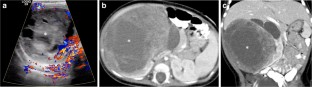

Fig. 1

Fig. 2

Fig. 3

Fig. 4

Fig. 5

Fig. 6

Fig. 7

Fig. 8

Fig. 9